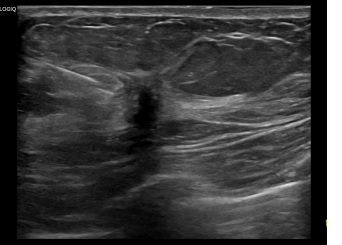

상기환자는 외부건진이상소견 조직검사위해 내원하신 60대 후반

여성분으로 의심스러운 우측유방혹 조직검사 시행해 유방암 진단되었습니다.